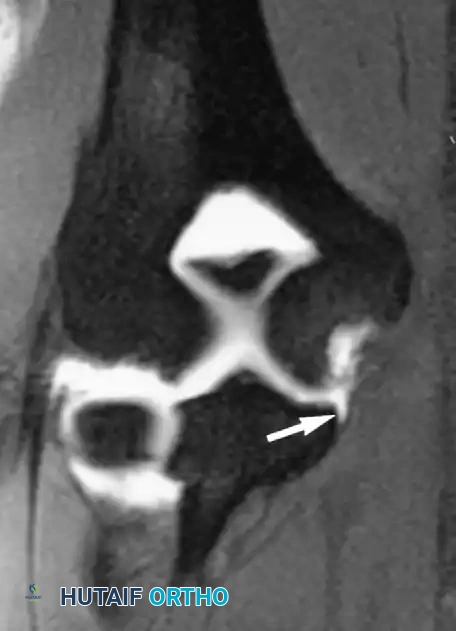

على صور الرنين المغناطيسي، يظهر التمزق الكامل كانقطاع مفاجئ في ألياف الوتر، وغالباً ما يكون مصحوباً بتراجع الوتر إلى الأعلى وتجمع للسوائل أو الدم حول منطقة الإصابة.

صورة رنين مغناطيسي توضح تمزق وتر العضلة ذات الرأسين البعيد وتراجعه